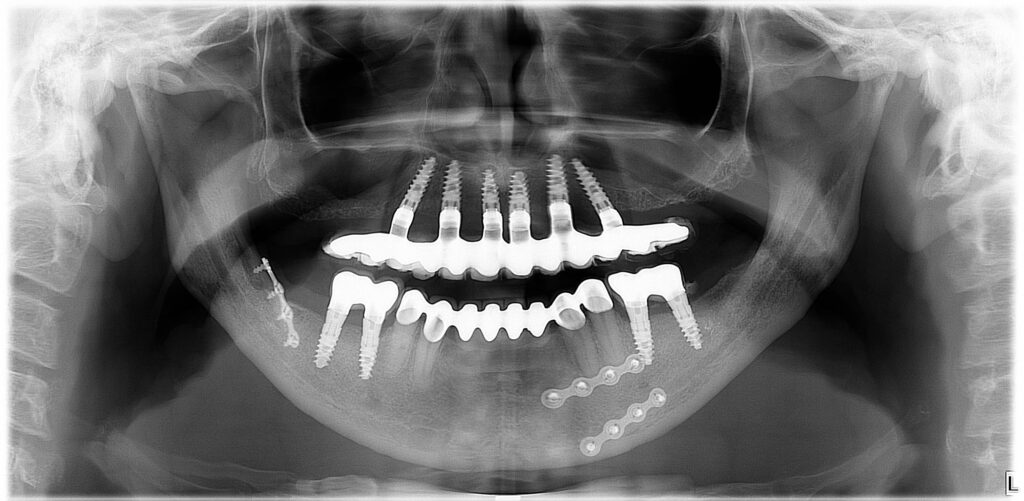

All-On-6 - Teljes rehabilitáció csavarozható, fix fogsorral, implantátummal

Az All-on-6 fogpótlás évek óta fennálló teljes foghiány esetén is ideális megoldás lehet, még akkor is, ha a csontvesztés előrehaladott állapotban van. Ezzel az innovatív fogászati megoldással visszaállítható a teljes rágóképesség, mintha csak saját fogait kapná vissza, és örökre elfelejtheti a kivehető fogsorát.

A csavarozható rögzítésnek köszönhetően a fosgsor és az implantátum kapcsolata bontható, így biztosítva a hosszú távú javíthatóságot.

A súlyos csontveszteség ellenére is sikerült páciensünknek fix, rögzített fogsort készíteni, a feslő állcsonton az All-on-4, míg az alsó állcsonton az All-on-6 implantációs megoldással, így visszakaphatta a rágás örömét.